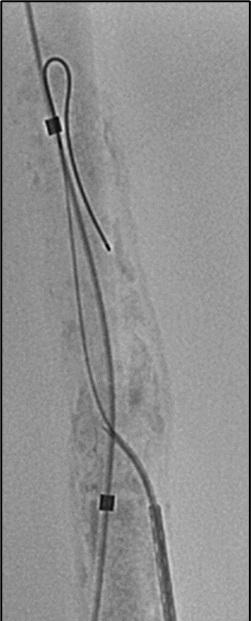

Pilot testing has shown that a new framework—dubbed Endo-STAR—can be used to describe and standardise endovascular interventions for peripheral arterial disease (PAD) within a randomised controlled trial (RCT) protocol and monitor adherence to the protocol over the course of a trial. Ewa M Zywicka (University of Bristol Medical School, Bristol, UK) shared this conclusion during the Prize Session at the recent European Society for Vascular Surgery (ESVS) annual meeting (24–27 September, Kraków, Poland).

ZYWICKA BEGAN BY NOTING THAT

rigorous evaluation of novel lower-limb endovascular interventions is “critically important” to ensure adoption of effective technologies and rejection of those that are ineffective or harmful.

The presenter continued that poor reporting of RCTs limits the evaluation of technologies for lower-limb endovascular interventions, highlighting a recent study in which more than half of RCTs did not adequately describe interventions, and almost 80% did not report any form of standardisation.

The aim of Zywicka and colleagues’ present study, therefore, was to develop a specific framework for describing and standardising endovascular lower-limb interventions within clinical trials.

Zywicka explained to the ESVS audience that the Endo-STAR framework was developed using qualitative research methodology and the Enhancing the Quality and Transparency of Health Research (EQUATOR) methodological framework. The presenter added that trial reports and associated protocols identified in a recent systematic review of endovascular infrainguinal lower-limb RCTs for PAD provided the data for developing the preliminary framework.

Going into more detail about the research methods used, Zywicka detailed that a framework approach to thematic analysis of qualitative data was employed to code and categorise text into steps and components of endovascular infrainguinal interventions.

Subsequently, focus groups were conducted

with key international stakeholders such as clinical practitioners—namely vascular surgeons, interventional radiologists, angiologists and cardiologists—trialists, industry representatives and journal editors to refine the framework and consider clarity and feasibility issues. Zywicka noted that the framework was updated based on this feedback, and

a consensus between stakeholders was reached via a modified Delphi-style questionnaire.

Finally, Zywicka shared, the framework was refined through cognitive interviews with trialists to test the real-world feasibility of using the Endo-STAR framework in contemporary endovascular RCTs. An online version of the Endo-STAR framework

Twenty-four key stakeholders participated in three focus groups, contributing to the refinement of the framework

was developed to facilitate implementation and dissemination.

At ESVS, Zywicka informed attendees that the preliminary framework was developed after including data from 112 RCTs evaluating endovascular infrainguinal interventions for PAD.

Zywicka relayed that 24 key stakeholders participated in three focus groups, contributing to the refinement of the framework, and all 24 participants took part in the consensus questionnaire. After the first round of the questionnaire, the presenter continued, an agreement above 85% was reached for each framework section. Ten trialists involved in contemporary endovascular trials took part in pilottesting the framework.

Ultimately, Zywicka reported, the Endo-STAR framework was structured into six main sections: 1) expertise of the professional delivering the intervention, 2) setting/location of the intervention, 3) anaesthesia provided for the intervention, 4) imaging used at the time of the intervention, 5) intervention components: access, crossing the lesion, treating the lesion (including specific steps and details related to all currently available endovascular devices) and closure of the artery, and 6) pharmacological interventions.

In discussion time following Zywicka’s talk, jury member Jon Boyle (Cambridge University Hospitals NHS Foundation Trust, Cambridge, UK) asked how the framework might help in terms of monitoring long-term outcomes of endovascular interventions, to which the presenter responded: “What we are aiming to achieve with this framework is to know what has been done in a trial […] we expect that actually being able to know and clearly describe what was done in a trial can be used to easily compare trials and even potentially compare results in the long term as well.”